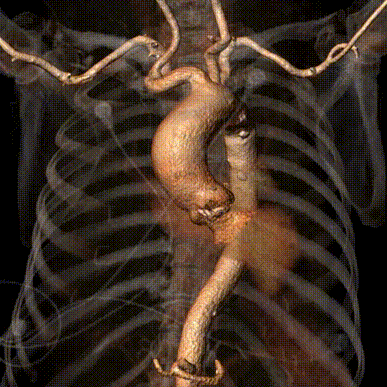

术前CT评估

• 先天二叶式主动脉瓣,瓣环径为23.7mm,瓣叶增厚伴重度钙化,钙化分布不均,主要分布于两窦交界处一侧;

• 冠脉开口高度可,切线角度测量未见冗长瓣叶;

• 瓦氏窦、窦管交界内径尚可,升主动脉扩张;

• 左室腔内径正常,心室壁增厚;

• 瓣环水平夹角为52°,主动脉弓宽度、角度尚可;

• 主动脉弓、腹主动脉下段、双侧髂总动脉可见散在钙化斑块,双侧髂总动脉局部附壁血栓,腹主动脉、双侧髂总动脉轻度扭曲,入路血管直径尚可。

CT动态预览

主动脉根部测量

瓣上结构测量

冠脉阻挡风险及左室大小评估

外周血管入路评估